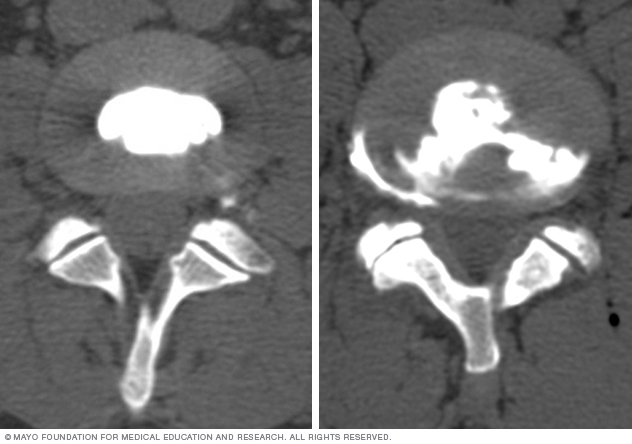

Discogram images

If the dye stays in the center of the disk, the disk is not damaged. If the dye spreads outside the center of the disk, the disk has undergone wear-and-tear change, which may or may not be painful.